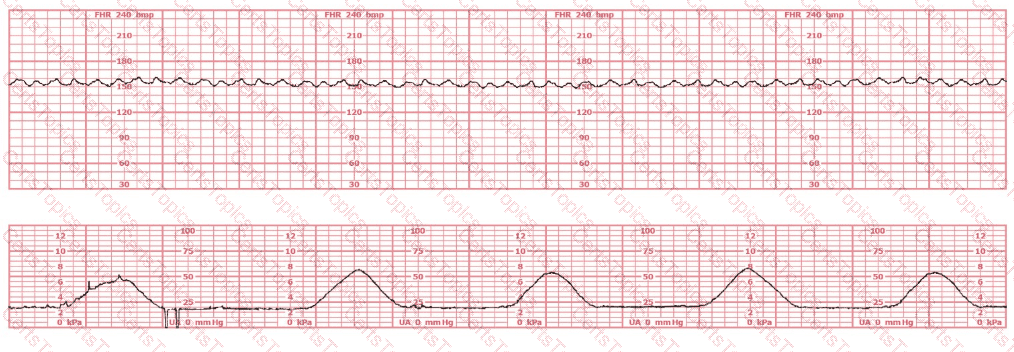

The tracing shown is a:

This tracing demonstrates:

This tracing would be categorized as a

This tracing reflects: